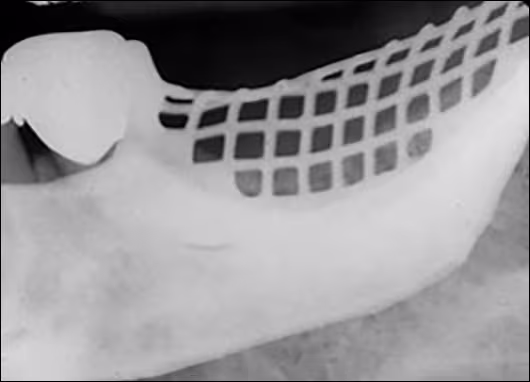

When a removable prosthesis is left in the mouth during exposure, an image of the appliance will appear superimposed over the teeth (Figure 31). Prior to radiographic procedures, ask the patient to take out all removable items from the mouth, such as retainers, partial dentures, complete dentures, and the like.

Figure 31: Mandibular Partial Denture